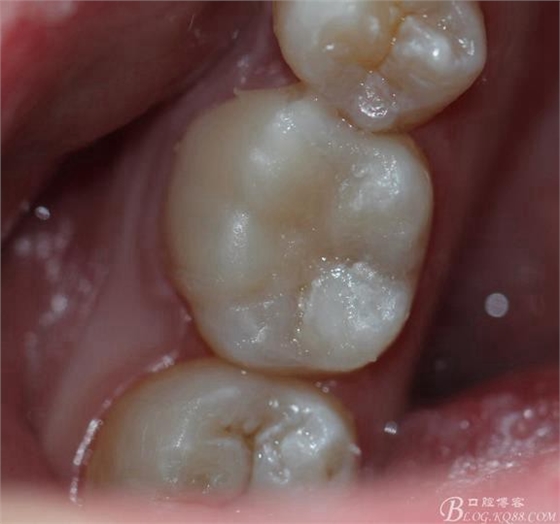

粘接 去除多余的粘結(jié)劑 進(jìn)行光照 調(diào)HE 一周后進(jìn)行拋光

粘接后X線片

復(fù)診拋光 很容易看到邊緣線,原因是主要有兩個(gè):一-瓷塊選擇不準(zhǔn)確,目前我們單位瓷塊顏色單一。二- 粘結(jié)劑,選擇和牙體顏色不一致的。我選擇的偏白,所以邊緣白線較明顯。

總結(jié):歷時(shí)2周時(shí)間結(jié)束,比較累。整體感覺沒有想象中那么好,總也做不出樹脂嵌體的那種渾然天成的感覺。